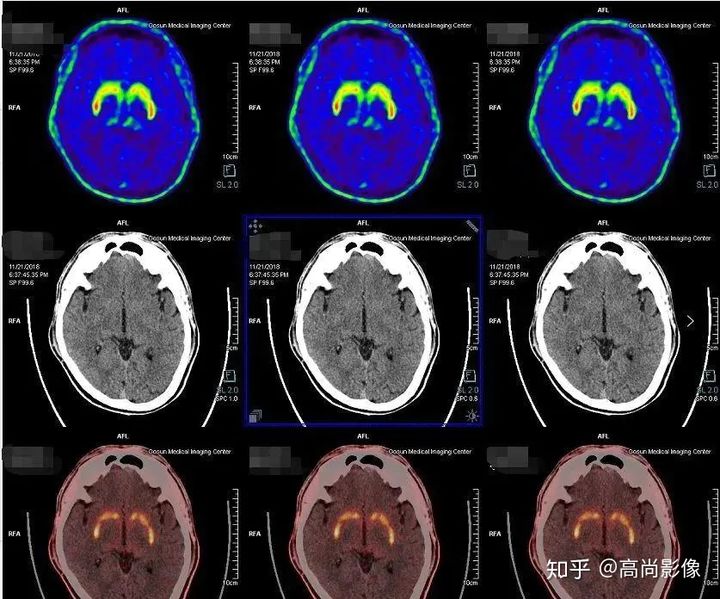

多巴胺轉(zhuǎn)運體顯像可以幫助鑒別診斷帕金森和良性震顫,具有良好的診斷效能。

1年多來,黃大爺?shù)碾p手總是抖個不停,他和家人都非常擔(dān)心。黃大爺來到中心進行了PET/CT的檢查,檢查發(fā)現(xiàn),黃大爺?shù)亩喟桶忿D(zhuǎn)運體顯像基本正常,最后,黃大爺被診斷為良性震顫。

雙側(cè)尾狀核、殼核多巴胺轉(zhuǎn)運體分布對稱、均勻

相比之下,童大媽就沒有這么幸運了。除了右邊身子總是抖動,童大媽還有嗅覺障礙、動作緩慢等癥狀。童大媽的PET/CT檢查結(jié)果符合帕金森的表現(xiàn),為臨床診斷提供了重要依據(jù)。

雙側(cè)尾狀核多巴胺轉(zhuǎn)運體分布對稱,左側(cè)殼核后部多巴胺轉(zhuǎn)運體分布較對側(cè)明顯減少,結(jié)合童大媽癥狀,先考慮帕金森。